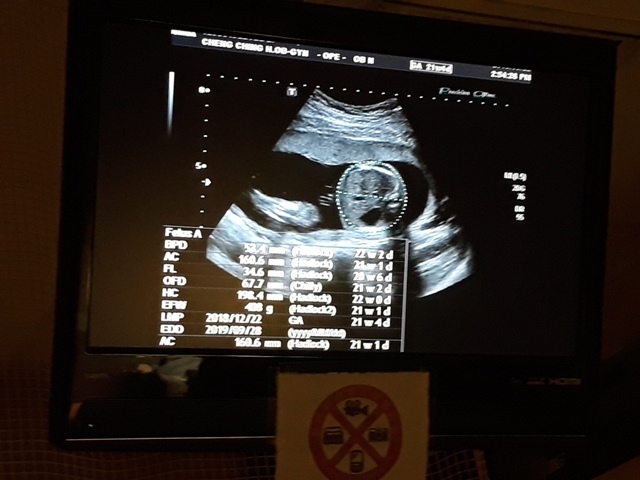

當小純進入診間看診時,我並沒有進去,因為小純說,有時男生不能進去,會被請出來。在外頭等待的我感到很緊張,不久之後,謢理人員請我進入診間,我嚇了一跳,想說發生什麼事了,進入之後,得知小純真的懷孕了,而且已懷了九星期又五天。看診的醫師說,驗孕棒第二條線淡淡的,沒想到胚胎照出來那麼大了,說Baby很健康。還說一閃一閃的是他的心跳,有頭、有手、有腳還有臍帶。小純後來說看了內心覺得很感動,才叫我一起進去看。

小純肚子裡的Baby超音波圖↓

進到超音波室後,發現幫小純照超音波的就是關醫師(小純原本以為會是超音波技術員,照完才會有醫師來,結果是關醫師從頭照到尾)。關醫師一項一項的幫小飛做檢查,雖然是高層次的超音波,比平常的產檢還仔細,但是很多東西我和小純都看不太出來,但是手、腳的指頭和脊椎都很清楚。

今天的高層次超音波照下來,小飛還蠻健康的,唯獨FL(大腿骨的長度)的成長,比目前實際的天數(21週又5天)還小(超音波照出來是20週又6天),不過還在正常值內,小純聽到這個消息心情有些Blue,問關醫師多喝牛奶能不能改善,關醫師卻叫小純不要喝太多牛奶:「牛奶喝多了,會有牛脾氣。」關醫師也不只一次的表示,希望孕婦不要吃太多,吃太多會讓小寶寶變大,這樣不利於生產,至於FL成長比較慢的事,關醫師說,孩子出生再補給足夠的營養或者運動即可。

| 2019年05月22日 | 53.4mm(28%) | 160.6mm(28%) | 34.6mm(20%) | 408g(69%) | 150 |

| BPD:胎兒頭骨橫徑 AC:胎兒腹圍的長度 FL:胎兒大腿骨的長度 EFW:胎兒的體重 括弧內百分比為較上次產檢的成長比例 | |||||

| 日期/項目 | OFD | AFI(4) | HC |

| 2019年05月22日 | 67.7mm | 17.9mm | 198.4mm |

| OFD:胎兒頭寬徑 AFI:羊水指數 HC:胎兒頭圍 | |||